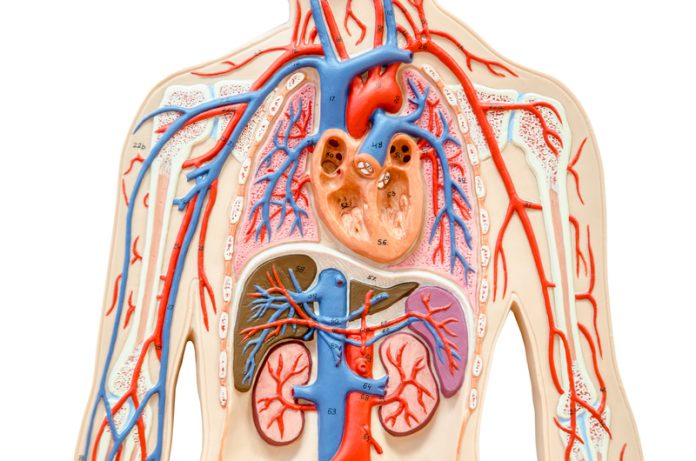

Many diseases can affect your kidney function by attacking and damaging the glomeruli, the tiny filtering units inside your kidney where blood is cleaned. Glomerular diseases include many conditions with many different genetic and environmental causes. Membranous nephropathy (MN) is a type of glomerular disease and is an autoimmune disease. An autoimmune disease is caused when your body’s defence system turns against you and harms your body when it should be protecting you.

Your defence system is known as your immune system, which is “turned on” by glomerular disease. MN is one of the most common causes of nephrotic syndrome. When your immune system attacks the glomeruli in membranous nephropathy, it causes changes to the filters that lead you to lose a large amount of protein into the urine. If this continues at high levels, it can eventually lead to kidney failure.